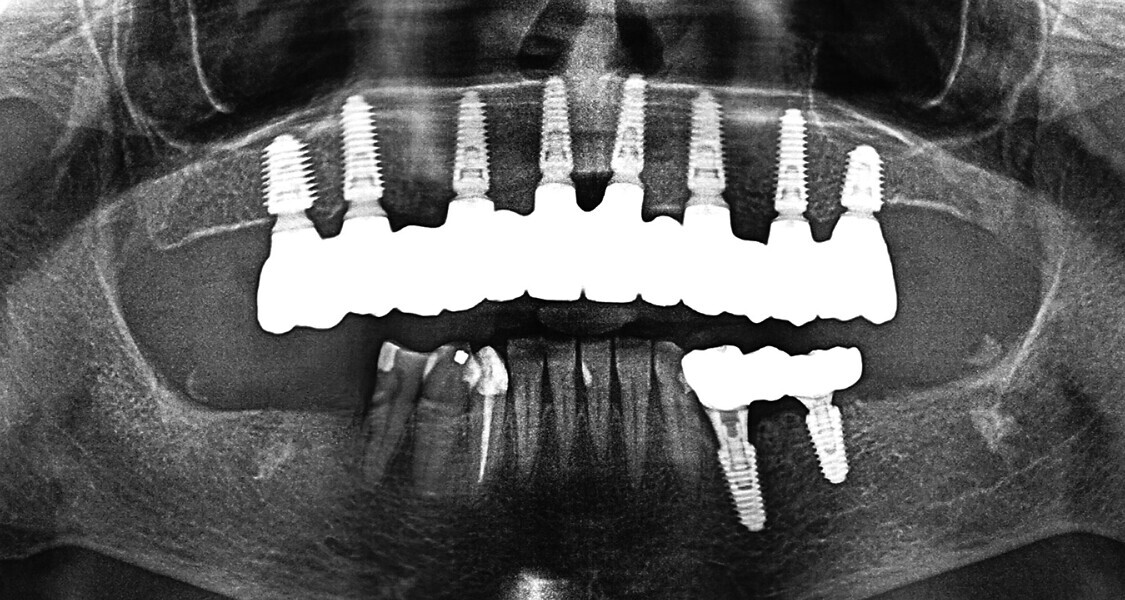

Fig. 16a: Panoramic radiograph showing printed restorations secured with Grammetry Vortex LA VIS screws.

Fig. 17a: Final panoramic radiograph confirming seating of the zirconia restorations.

The data collected was sent through a scanning software portal (Medit Scan for Clinics) to the dental laboratory with requested changes for correction of the desired smile design. Utilising advanced planning features in the design software (exocad), the midline and tooth size changes were corrected. 3D-printed maxillary and mandibular PMMA restorations were used for try-in using the direct-to-MUA screws (Vortex LA VIS; Fig. 16a). Fit, phonetics, aesthetics and occlusion were evaluated and confirmed using digital articulation (OccluSense; Fig. 16b). The patient was extremely satisfied with the printed try-ins. Since no adjustments were required, the patient was allowed to leave with the printed try-ins as new provisional restorations made from extra-strong resin. The new provisional restorations were worn for ten days to confirm form and function. The final shade was chosen, and metal-free monolithic zirconia restorations were then fabricated by the laboratory.

The final restorations were passively and accurately seated ten days later uneventfully using Vortex LA VIS screws. Confirmation records were taken with photographs, radiographs and digital articulation to recheck fit, function, phonetics and occlusion (Fig. 17a). The patient was extremely satisfied with his final restorations, describing the process as life-changing and surprisingly fast in comparison with what he had heard about full-mouth implant therapy. He was especially pleased with the speed at which the final process was able to be completed (Figs. 17b & c).